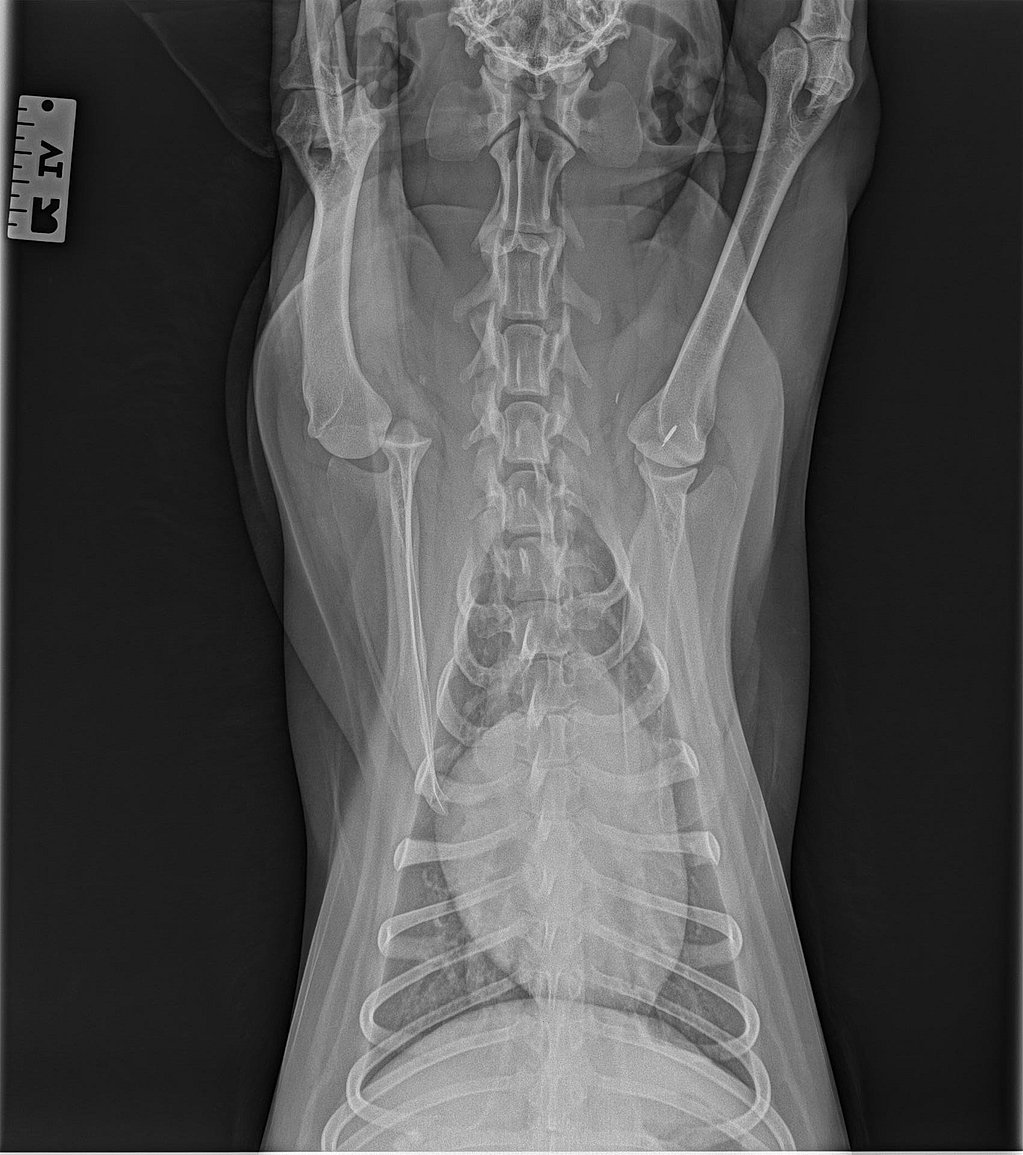

Des radiographies du thorax et du membre thoracique droit ont été réalisées à l’admission (vues latérales et dorso-ventrale).

Les clichés montrent :

- Une luxation latérale évidente de la tête humérale par rapport à la cavité glénoïde.

- Un déplacement de la tête humérale vers l’extérieur, sans fracture humérale ou scapulaire associée.

- Des contours osseux nets, compatibles avec une luxation évoluant depuis plusieurs jours.

- L’absence de lésion thoracique significative.

Ces images confirment la luxation chronique non réductible, orientant vers une stabilisation chirurgicale.